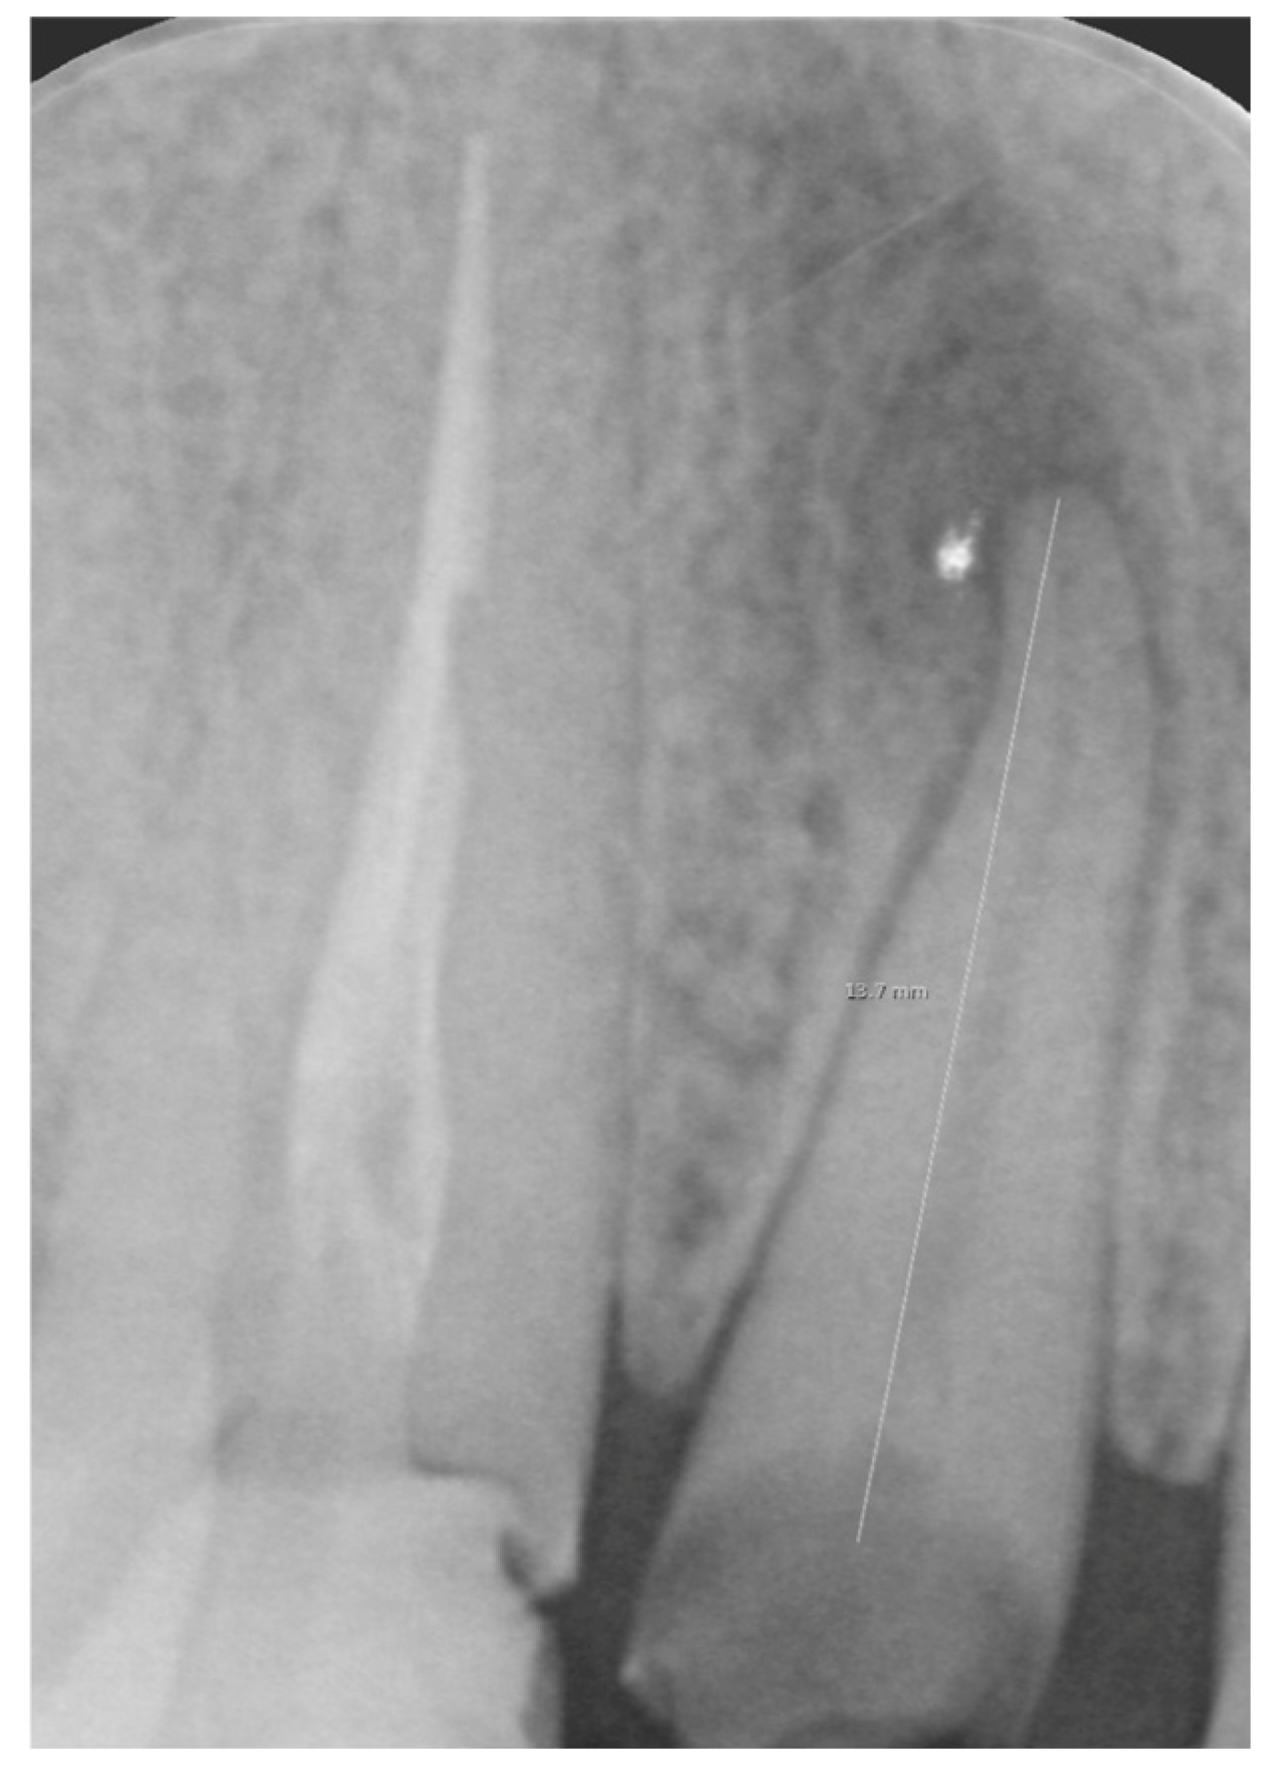

Figure 1.

Intraoral x-ray of a tooth with a destructive carious lesion.